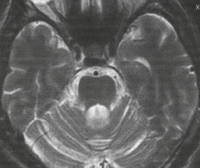

На МРТ головного мозга при спиноцеребеллярной атаксии обнаруживаются очаги демиелинизации и нейродегенерации в области полушарий, червя мозжечка и базальных ядер. На терминальных стадиях развития заболевания может отмечаться полная атрофия мозжечка. Молекулярно-генетические исследования при спиноцеребеллярной атаксии сводятся к поиску патологически увеличенного количества сAG-повторов в генах, ассоциированных с этим заболеванием. В настоящее время большинство лабораторий мира осуществляет поиск этого дефекта в генах, наиболее часто приводящих к развитию патологии - ATXN1, ATXN2, ATXN3, ATXN7, ATXN8 и сACNA1A.